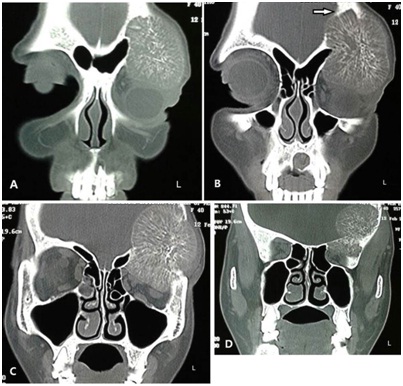

Our initial suspicion based on the clinical appearance of the swelling was that of a fibro-osseous lesion. Subsequent CT of the skull and orbits [Table/Fig-2a-d] revealed a well-demarcated, contrast-enhancing, expansile osteolytic lesion arising from the frontal bone. It was about six cm in greatest dimension, and involved both the outer and inner tables. The lesion had a thin sclerotic rim, especially prominent where it abutted against the dura pushing it medially towards the frontal lobe but without causing midline shift. It showed multiple trabeculae arranged radially, moving centrifugally from a sclerotic osseous core, forming a “sun-burst” or “sun-ray” appearance. The left orbital roof was breached and the lesion encroached the orbital compartment resulting in proptosis. The CT features were highly suggestive of a haemangioma [3,4], and we had to revise our provisional diagnosis.

CT-scan shows a lytic lesion arising from the frontal bone that enhanced with contrast. The serial bone windows (from anterior to posterior) (a-d) show the spherical lesion to erode the external table of the calvarium (a) and progressing postero-medially to erode the inner table as well (b {arrow}). Inside the mass, the bony trabeculae radiate centrifugally from a sclerotic centre, forming the classic “sun-burst” or “sun-ray” pattern (c). The lesion has a thin sclerotic rim that is prominent at its medial convexity where it abuts against the dura causing compression over the frontal lobe but without any midline shift (c,d). The left orbital roof is breached and the lesion encroaches the orbital compartment resulting in proptosis (a,b)